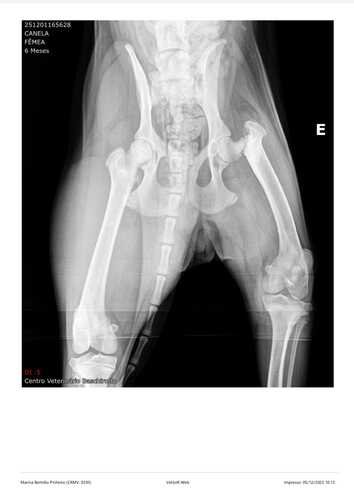

Após passar por avaliação veterinária, foi constatado que ela está com fratura no fêmur esquerdo e luxação de patela, e por isso precisa passar por uma cirurgia o quanto antes.